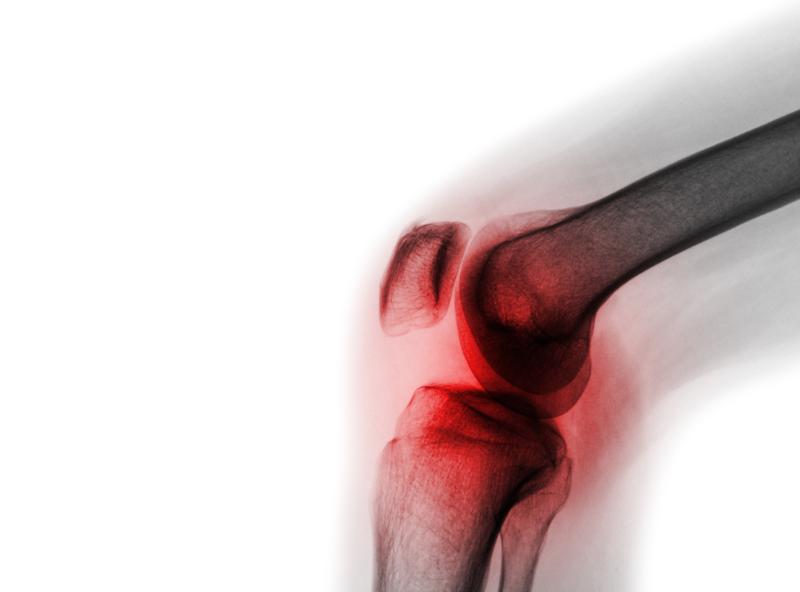

Weight-bearing recreational physical activities may lead to knee osteoarthritis (OA) in individuals with low levels of lower-limb muscle mass, according to a study.

Over a mean follow-up of 6.33 years, radiographic knee OA was detected in 793 or 9,483 knees (8.4 percent). Weight-bearing activity showed a positive association with the odds of incident radiographic knee OA (odds ratio [OR], 1.22, 95 percent confidence interval [CI], 1.10–1.35; p<0.001). No association was found for nonweight-bearing activity (OR, 1.04, 95 percent CI, 0.95–1.15; p=0.37).

In an analysis stratified by lower-limb muscle mass index (LMI), the association between weight-bearing activity and incident radiographic knee OA was seen only among participants in the lowest LMI tertile (OR, 1.53, 95 percent CI, 1.15–2.04; p=0.003).